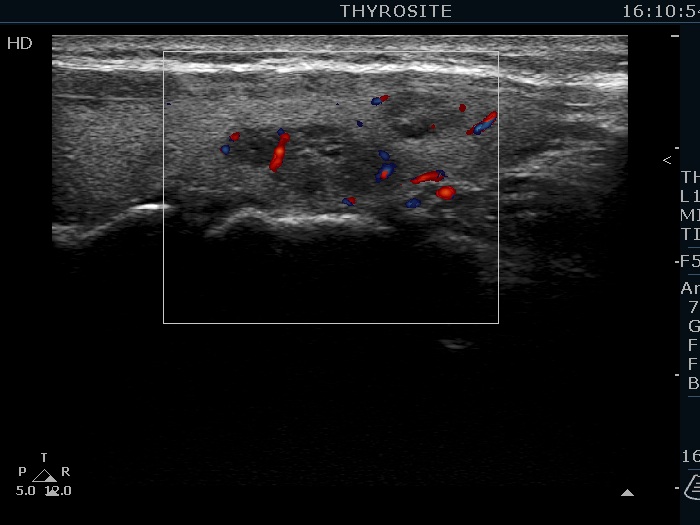

Ultrasonography. The thyroid was echonormal. There were several hypoechoic nodules in the left lobe. The middle one had back wall cystic figures. There were 3 or four discrete, deeply hypoechoic lesions above and lateral to the left lobe in the neck. One of them presented with a hilum-like figure while the others lacked hilum.

The lymph nodes had a non-typical presentation. They lacked a regular hilum.